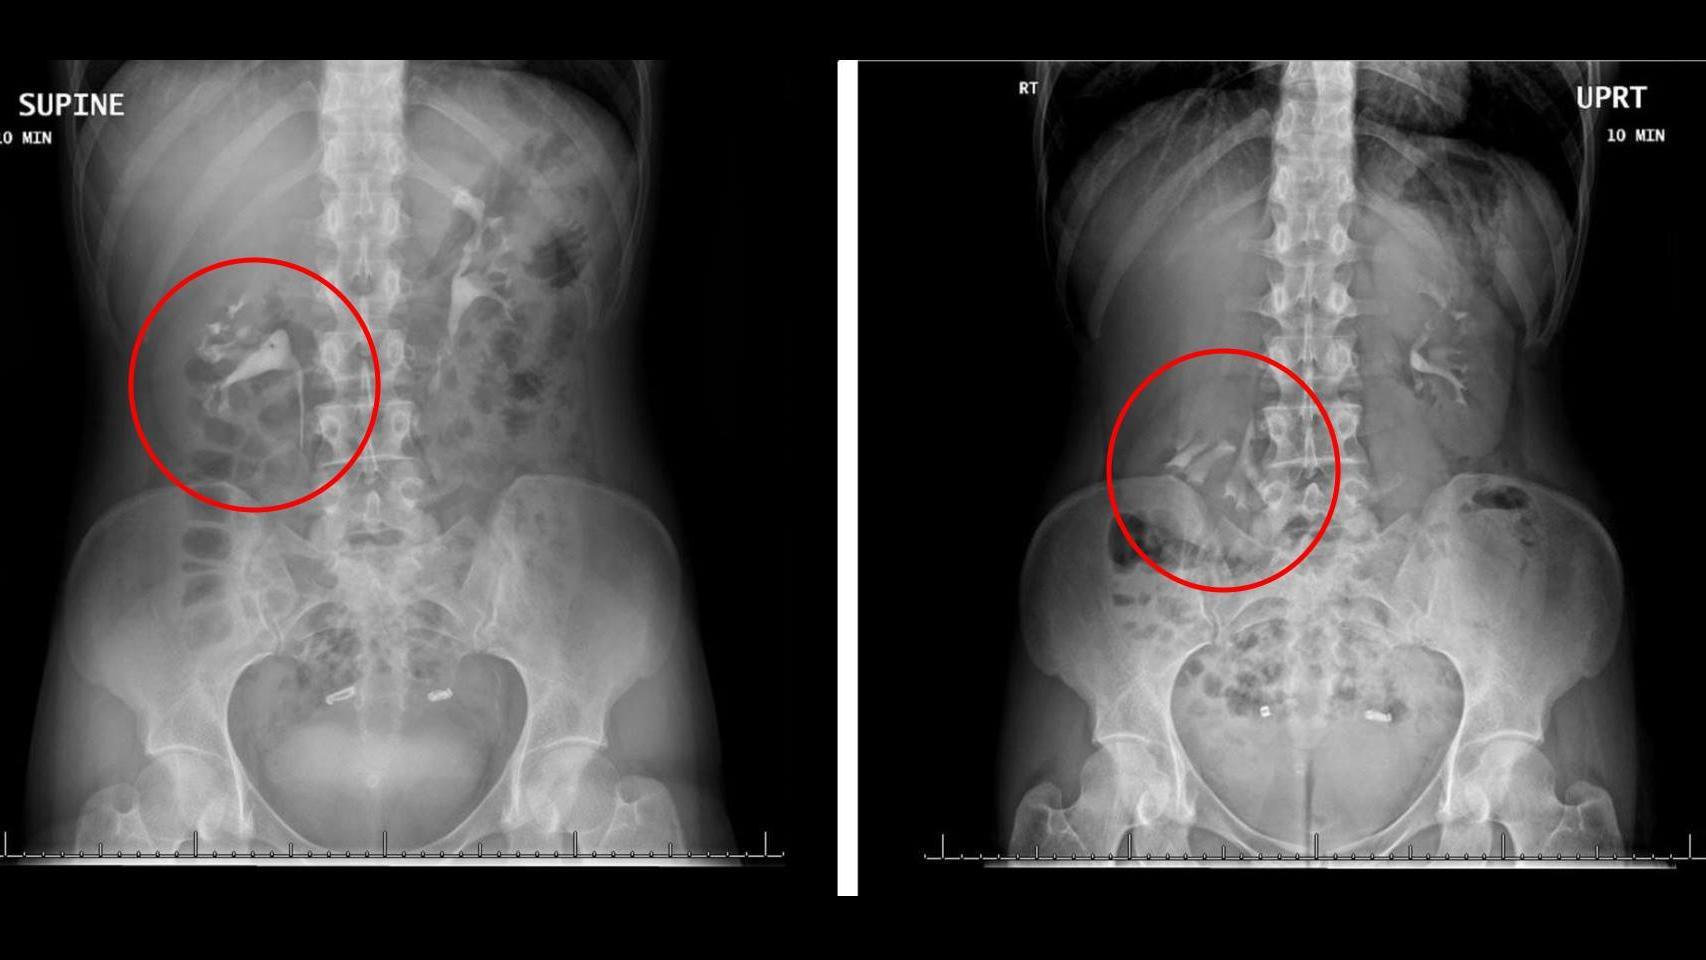

La pielografía intravenosa, clave para el diagnóstico

Se dice que una persona tiene nefroptosis cuando su riñón se desplaza una longitud superior a los cinco centímetros. En el caso de esta chica, las pruebas que le realizaron demostraron que llegaba a superar los seis centímetros, por lo que el diagnóstico era claro.

Según informan en BMJ Case Reports, la prueba clave fue la pielografía intravenosa, un examen radiológico que se usa habitualmente para detectar anomalías en los riñones, la vejiga y la uretra. Los médicos a cargo del caso aseguraron que esta prueba permite conocer a fondo la anatomía dinámica del paciente, por lo que fue esencial para el diagnóstico.